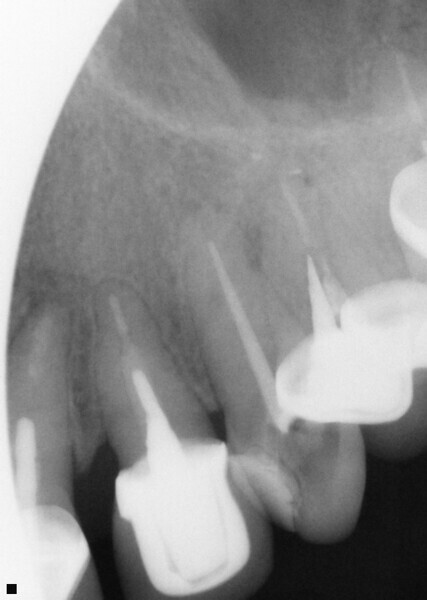

Fig. 14: Patient presented with complaint of pain on chewing on teeth 14 and 15 with increasing sensitivity to hot.